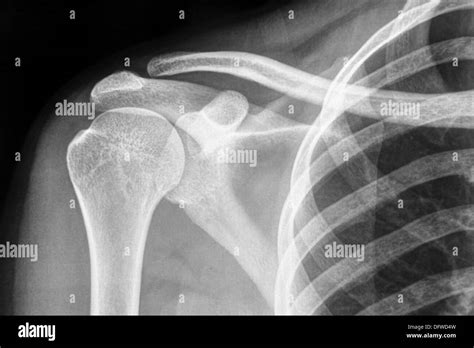

The acromioclavicular (ac) joint links the axial skeleton to the upper extremity, functioning in concert with the rest of the shoulder girdle to ensure. The standard axial view of the clavicle is taken. Web ap radiograph of a normal left clavicle.

To help pinpoint the location of the fracture; To help pinpoint the location of the fracture; Web the clavicle is an unusual long bone with many unique embryologic features. Both the ac and sc joints are visible (arrows) and the entire clavicle is seen.